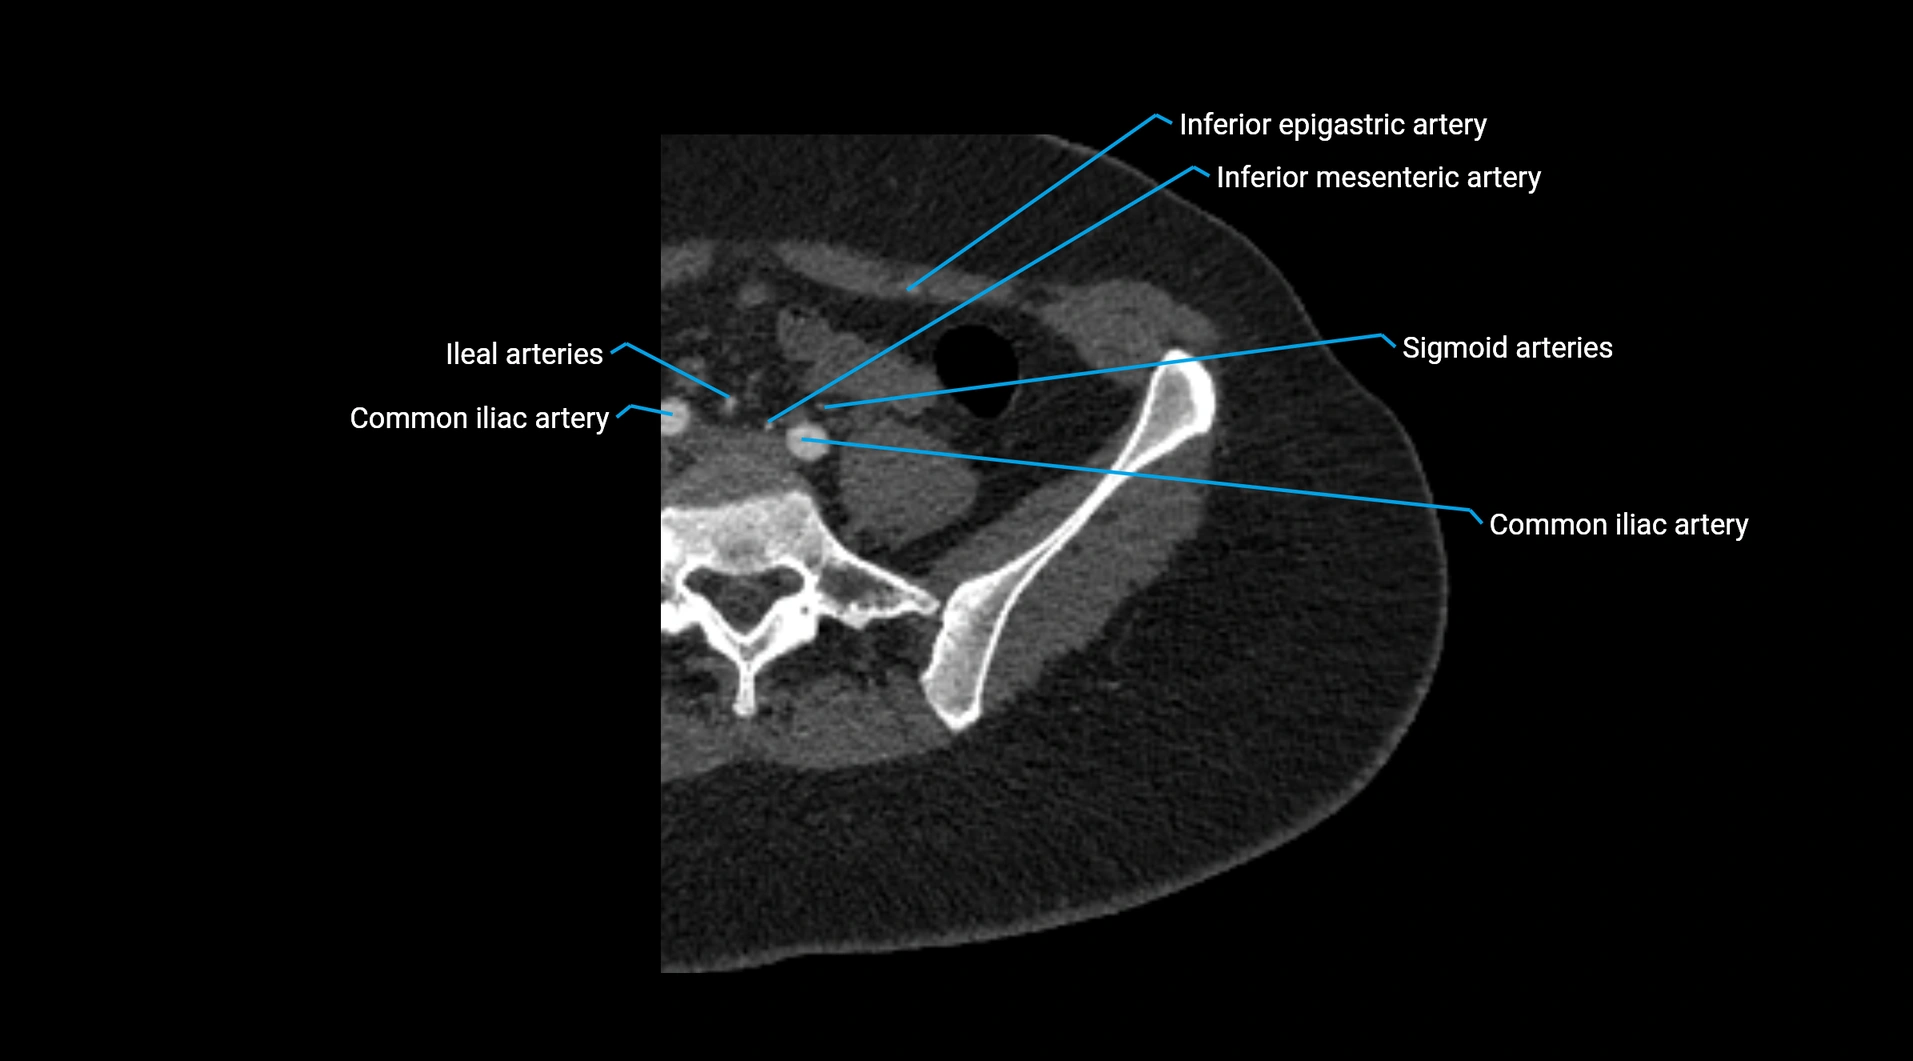

CT Appearance

Non-contrast CT:

• Appears as a tubular soft tissue structure anterior to vertebral bodies

• Calcified atherosclerotic plaques appear as hyperdense foci along the wall

• Useful for screening abdominal aortic aneurysm (AAA) size and mural calcification

Contrast-enhanced CT (CTA):

• Gold standard for abdominal aortic imaging

• Provides excellent detail of lumen, wall, aneurysm, thrombus, and branch vessels

• Multiplanar and 3D reconstructions help in aneurysm measurement, stent graft planning, and dissection evaluation

• Detects acute rupture, traumatic injury, or occlusion with high sensitivity